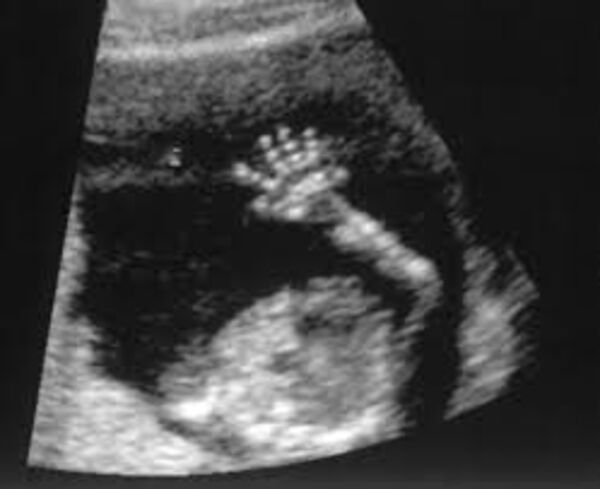

Bebekler anne karnında ne yapar?